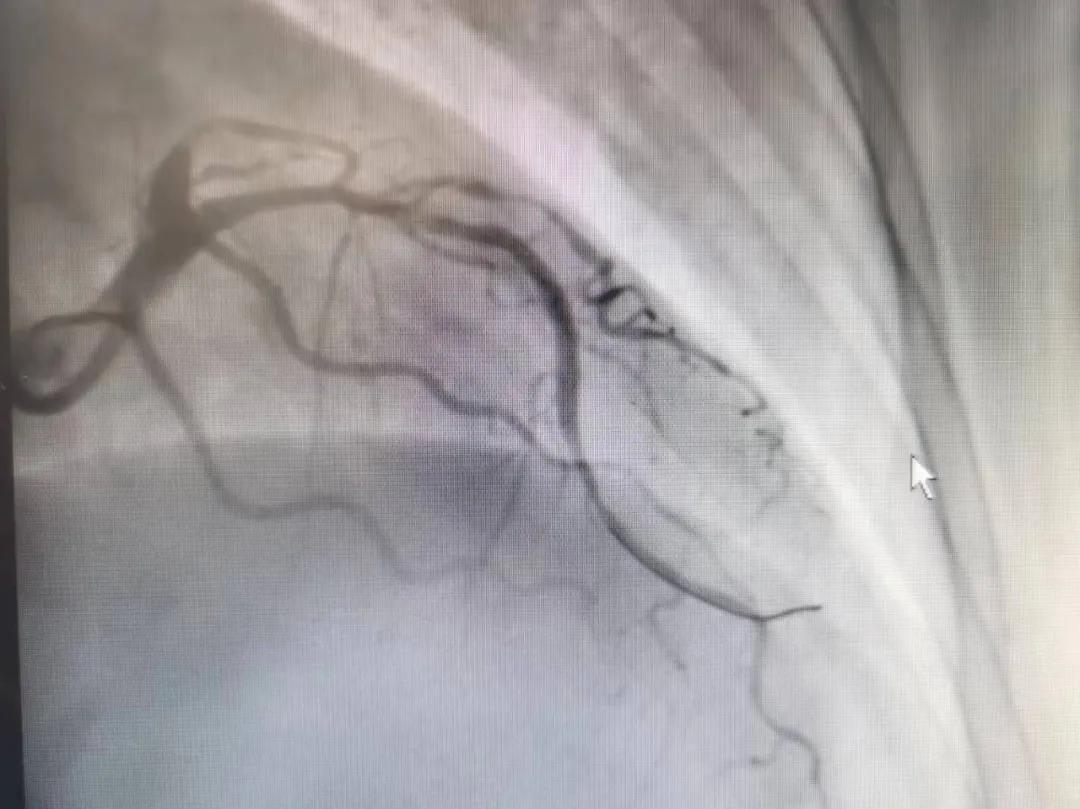

病人是位六十多歲的女性患者,有長期高血壓病史,1個月前開始出現(xiàn)胸悶胸痛,口服藥物治療效果不佳,經(jīng)朋友介紹,來到市二院心血管內(nèi)科。入院后完善冠狀動脈造影提示:前降支全程彌漫性狹窄伴鈣化,最重95%,回旋支狹窄約85%,右冠脈全程狹窄伴鈣化,最重60%。血管內(nèi)超聲顯示右冠脈開口面積3.36mm²,可見環(huán)形鈣化,考慮患者病變程度重、鈣化明顯,常規(guī)器械無法實現(xiàn)病變的良好預(yù)處理,且有很高的冠脈穿孔、血管夾層的風(fēng)險。

術(shù)前